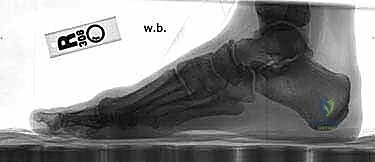

Effective preoperative planning is the cornerstone of a successful outcome. We evaluate a series of weight-bearing radiographs: AP and lateral views of the foot.

- Radiographic Analysis:

- Metatarsal Length: We assess the relative lengths of the metatarsals. Significant shortening of the first metatarsal can lead to transfer metatarsalgia postoperatively. While this osteotomy typically results in minimal shortening (average 0.98 mm), it's a factor to consider.

- Intermetatarsal Angle (IMA) and Hallux Valgus Angle (HVA): These are our primary measurements to quantify the deformity and guide the osteotomy's magnitude.

- Joint Congruency: We look for any subluxation or incongruity of the first MTP joint.

- Medial Eminence Size: This dictates the extent of our bunionectomy.

- Sesamoid Position: We note the lateral displacement of the sesamoids, which should ideally reduce with successful correction.

- Templating the Osteotomy: We routinely mark the proposed osteotomy directly on the radiograph. This allows us to visualize the wedge to be resected, its apex location, and the desired amount of correction. This mental rehearsal is invaluable.

FIG 2 • A–D. Preoperative and postoperative radiographs.